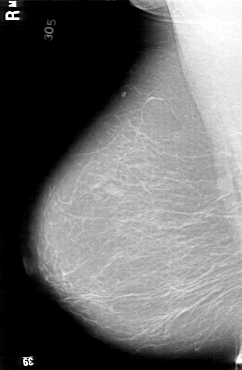

D_4194_1.RIGHT_MLO

LEFT_MLO LINES 6361 PIXELS_PER_LINE 4471 BITS_PER_PIXEL 12 RESOLUTION 43.5 OVERLAY

FILE: D_4194_1.LEFT_MLO.OVERLAY

TOTAL_ABNORMALITIES 1

ABNORMALITY 1

LESION_TYPE CALCIFICATION TYPE PLEOMORPHIC DISTRIBUTION SEGMENTAL

ASSESSMENT 0

SUBTLETY 4

PATHOLOGY BENIGN

TOTAL_OUTLINES 1

BOUNDARY